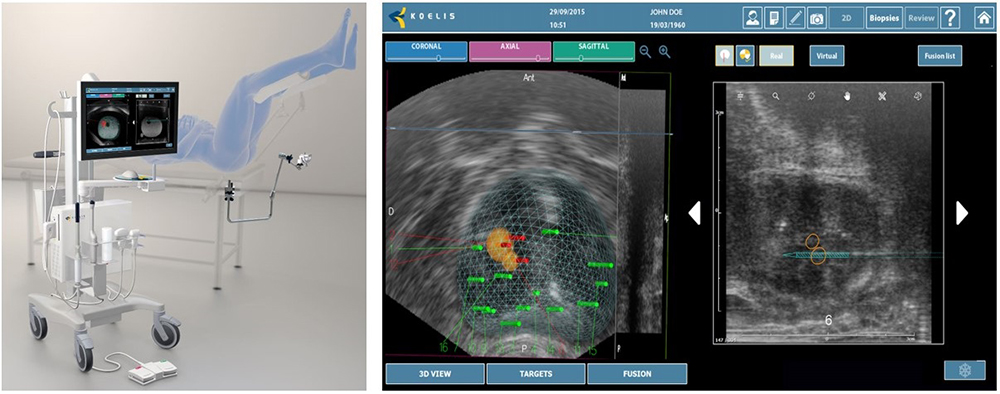

上記の問題点を解決するため、当科ではトリニティを導入いたしました。トリニティは事前に撮像されたMRI画像に、3Dの超音波画像をコンピューターでリアルタイムに融合させることにより、MRIと超音波の3D融合画像を作ることができる装置です(図3)。

この3D融合画像に癌が疑われる場所を映すことで、どこをターゲットとして生検すればよいかが鮮明にわかるようになります。しかも、トリニティはVirtual biopsy mode を使用して、実際の穿刺前に生検位置のシミュレーションが可能で、また3D マッピングにより生検した部位を可視化し、生検部位の記録を3D画像で正確に残すことが可能なため、ターゲットを外した場合でもやり直すことができるようになりました。